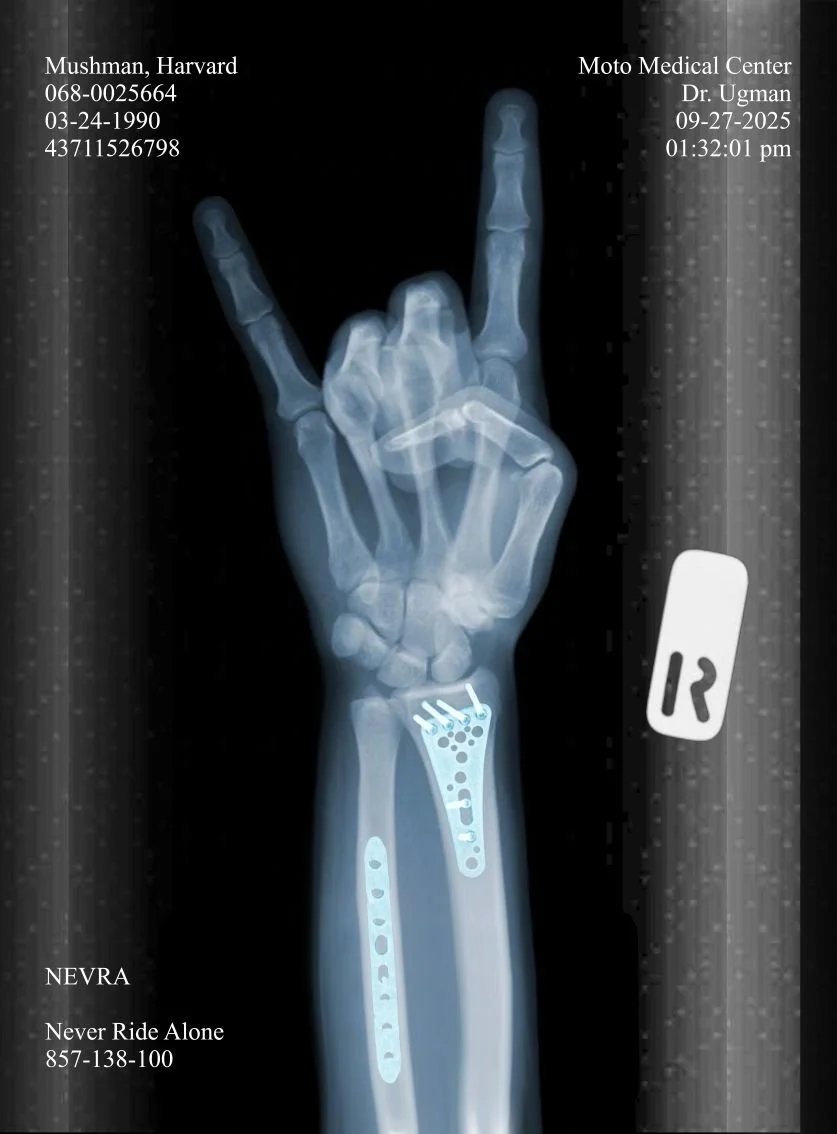

Because I live in Wyoming, specialists are few and far between, so it took a couple days of calling around, scheduling and vetting to find someone I trusted to put me back together. Finally 12 days after the accident, I had surgery to put the collar bone back together and was finally on the mend. What better way to celebrate than to wake up the following morning and go to the final WORRA race of the year. I’m far from professional, but I’m a rider none the less and live and breath this sport. I will always strive to support the riding community through my involvement in the racing community and in my continued efforts to grow the NEVRA community.